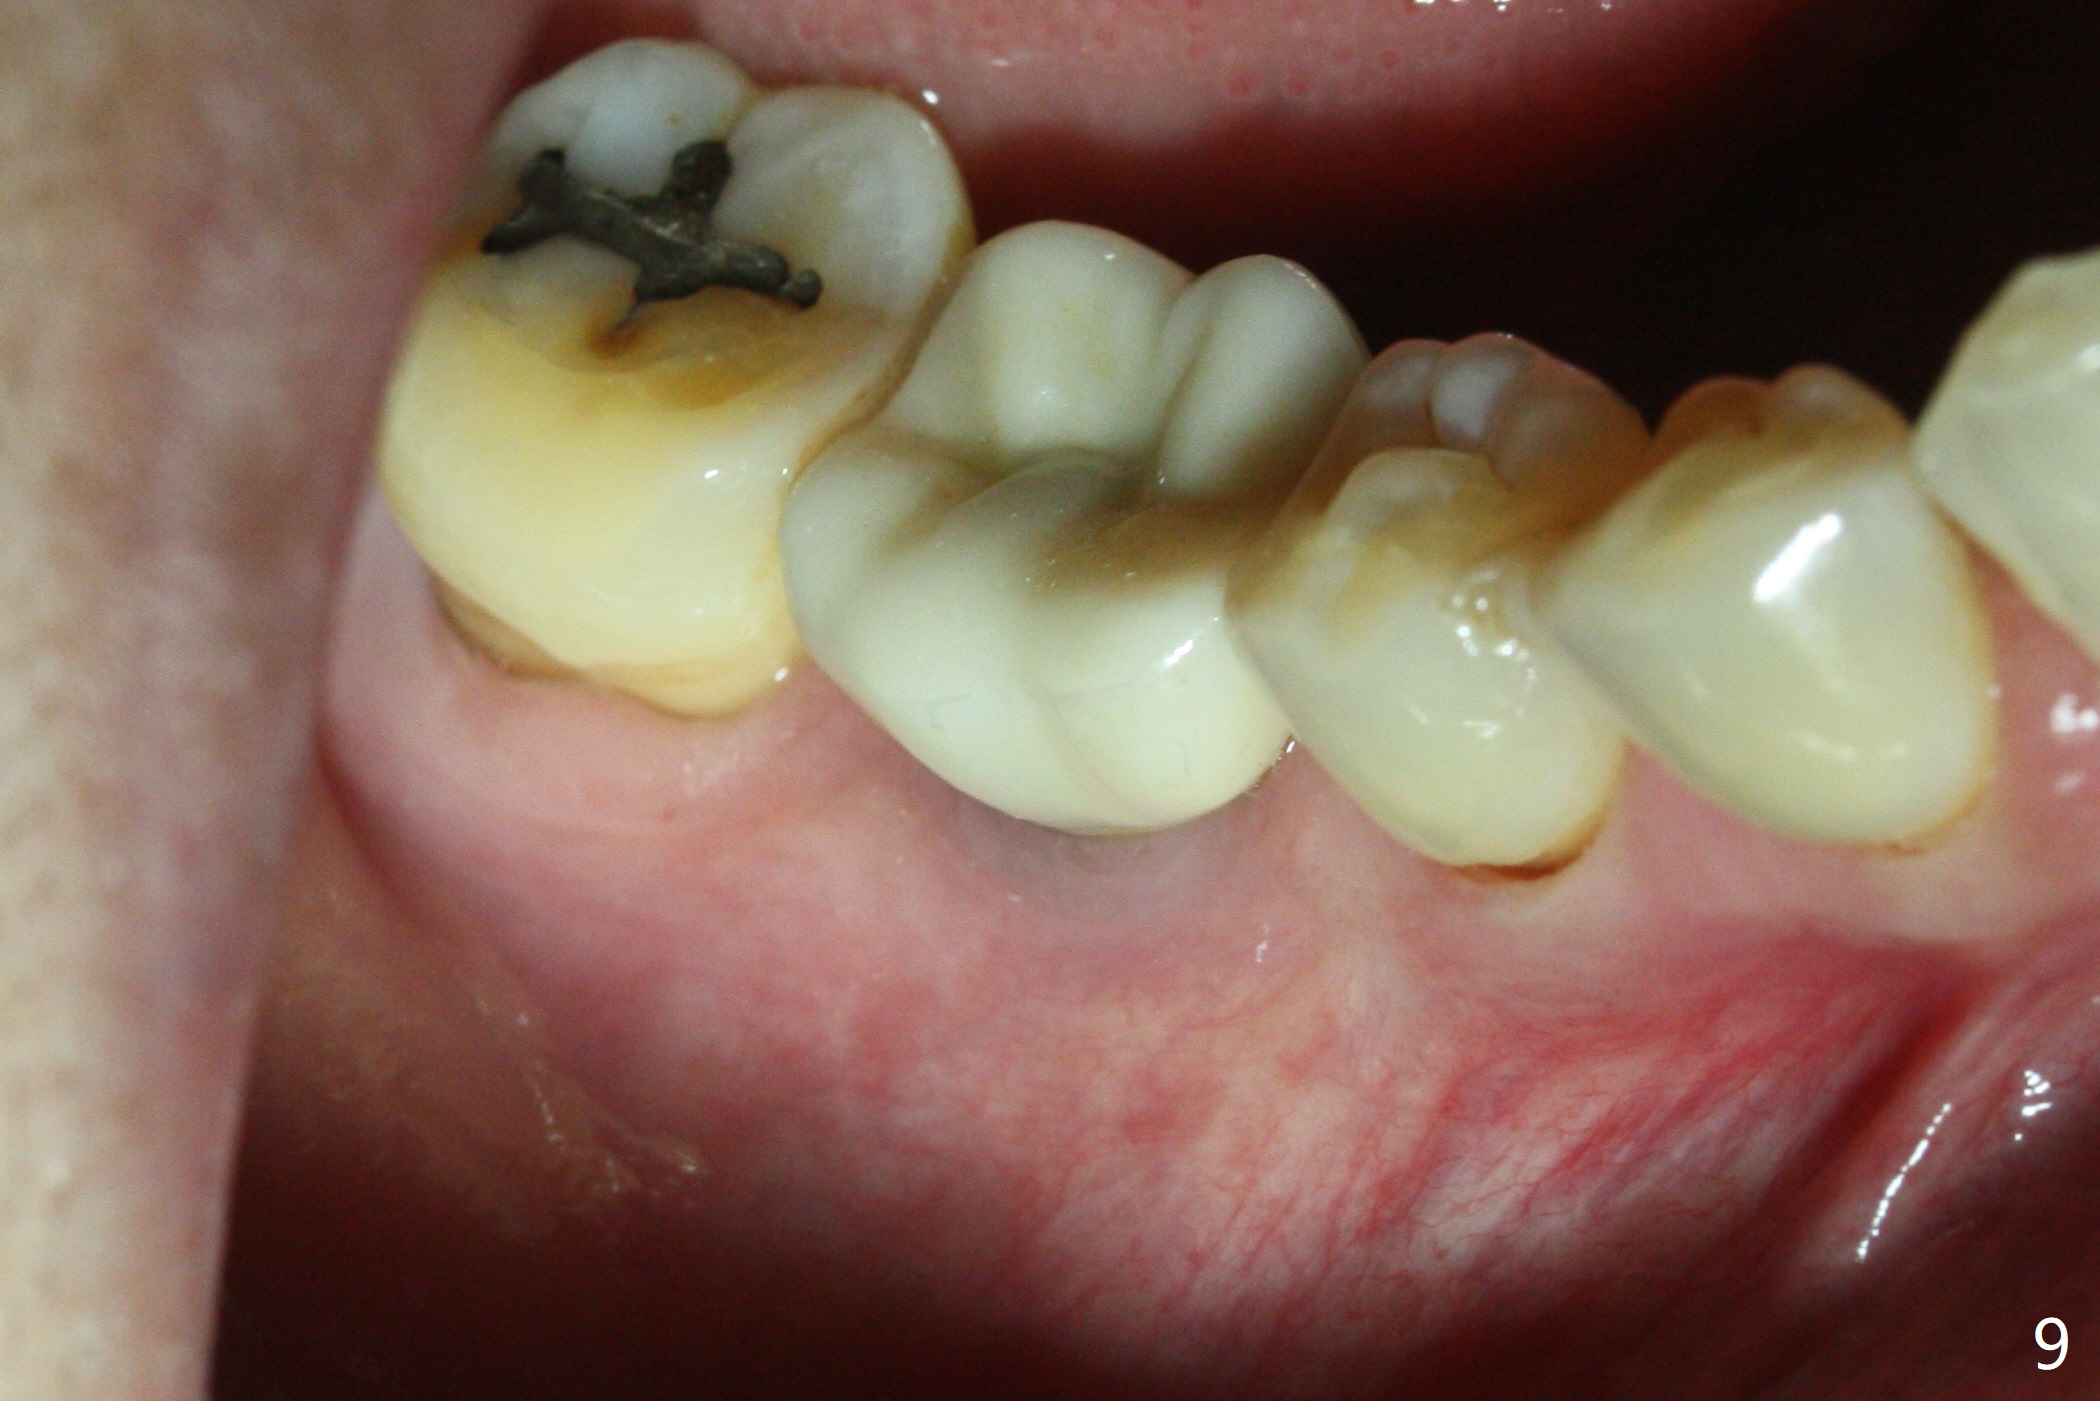

Thirteen months post bone graft via buccal approach, the patient has remained asymptomatic. There is no sign of infection buccally (Fig.1), but the lingual gingiva is erythematous (Fig.2 arrowheads) with deep pocket (Fig.3). Since the patient will be out of country for 7 months, exploration is going to be done immediately. Preop PA reveals mesial bone loss (Fig.4 M).

Upon flap reflection and granulation tissue curettage, the lingual threads are shown to be exposed with mesial bone resorption (Fig.5 <). The lingual defect is soaked with Clindamycin saturated gauzes (Fig.6 *), followed by copious irrigation, Emdogain application, bone graft and collagen dressing. The flap is sutured and covered by perio dressing.

The chronic infection with bone loss is probably due to two factors. No bone graft was placed at the time of immediate implant. The infection might come from the extraction site (due to incomplete debridement of the socket) or from a remote area: #9 endo perio lesion.

There is no symptom or sign of periimplantitis 3 years 8 months post 2nd bone graft (Fig.7-10). However, the patient complains of gingival hemorrhage 8 months later (Fig.11,12 (buccal), 13 (lingual view)). Water Pik is recommended.